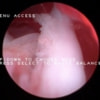

関節鏡検査を実施いたしました。関節鏡検査では、重度の滑膜炎および前十字靭帯の完全断裂が認められました。半月板に損傷は認められませんでした。

関節穿刺を行い、好中球はなく、少数のマクロファージや滑膜細胞が認められるました。膝蓋骨脱臼および前十字靭帯断裂による退行性の関節炎を疑い、関節鏡検査を実施いたしました。関節鏡検査では、重度の滑膜炎および前十字靭帯の完全断裂が認められました。内外側とも半月板に損傷は認められませんでした。

半年にわたる左後肢の跛行が認められるとのことで来院されました。触診にて左膝関節の疼痛、内側部の腫脹、膝蓋骨の内方脱臼を認めました。レントゲン検査にてfat pad signを伴う関節炎が認められたことから、前十字靭帯断裂と膝蓋骨内方脱臼( GradeⅢ)の併発と診断し、手術を行いました。術中の関節鏡検査にて前十字靭帯の完全断裂を確認、関節液検査にて感染を除外した後、TPLOと、滑車溝形成を始めとした膝蓋骨脱臼整復術を実施いたしました。